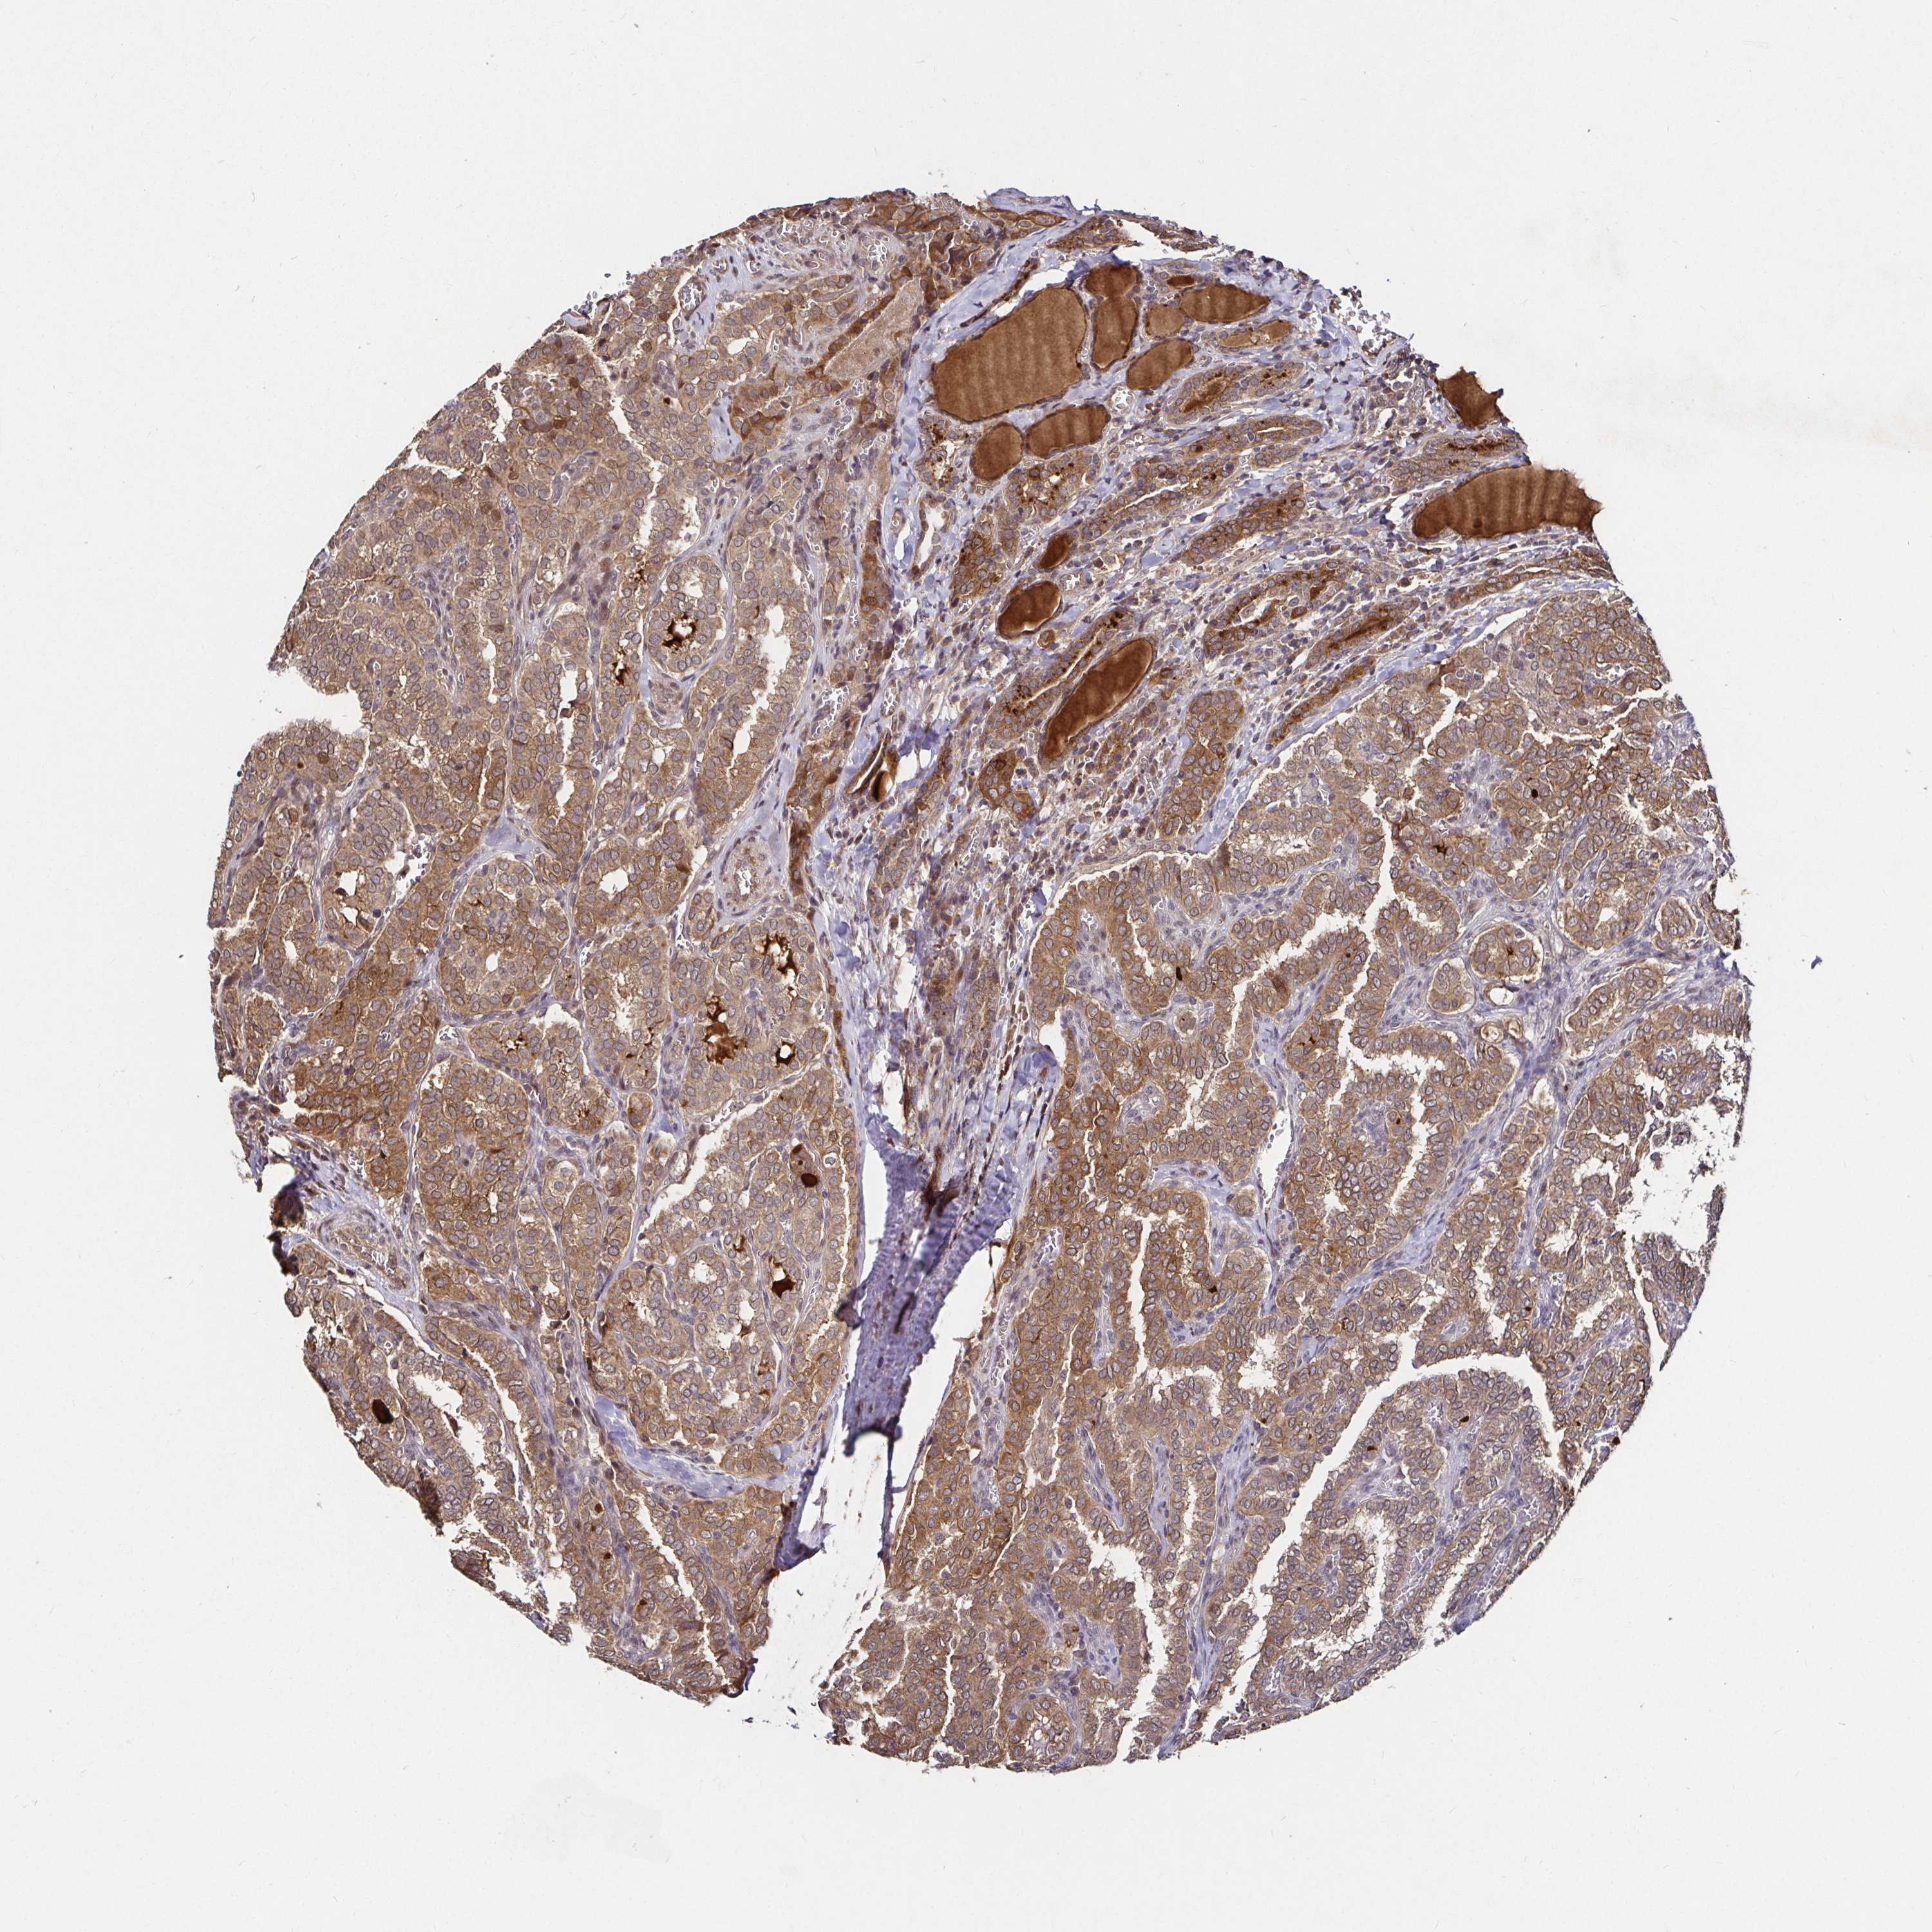

THYROID CANCER - Protein expressioni

A mouse-over function shows sample information and annotation data. Click on an image to view it in a full screen mode. Samples can be filtered based on level of antibody staining by selecting one or several of the following categories: high, medium, low and not detected. The assay and annotation is described here.

Note that samples used for immunohistochemistry by the Human Protein Atlas do not correspond to samples in the TCGA dataset.

Antibody stainingi

Antibody staining in the annotated cell types in the current human tissue is reported as not detected, low, medium, or high, based on conventional immunohistochemistry profiling in selected tissues. This score is based on the combination of the staining intensity and fraction of stained cells.

Each image is clickable and will lead to virtual microscopy that enables deeper exploration of all samples and also displays staining intensity scores, fraction scores and subcellular localization as well as patient and tissue information for each sample.

Antibody HPA045821

Antibody HPA054352

Antibody CAB012229

Staining

High

Medium

Low

Not detected

Intensity

Strong

Moderate

Weak

Negative

Quantity

>75%

75%-25%

<25%

None

Location

Nuclear

Cytoplasmic/membranous

Cytoplasmic/membranous,nuclear

Papillary adenocarcinoma, NOS

Follicular adenoma carcinoma, NOS